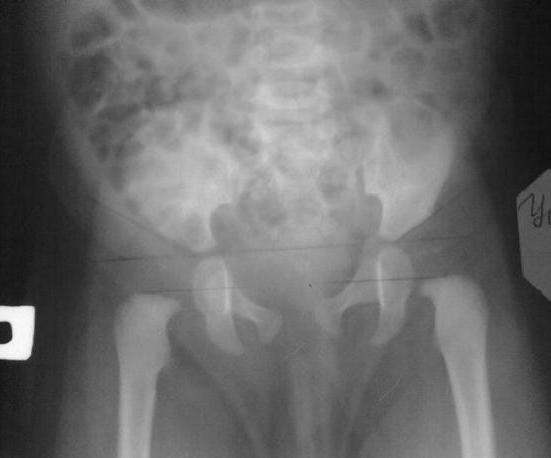

Нам 2 мес 5.09.10 будет 3.девочкаПоставили дисплазию тбс. Специалистов в городе нет и очень бы хотелось услышать ваше мнение.

По рентгену:ядер окостенения головок бедренных костей не определяется.Ацетобулярные углы симметричные 34 градуса, Величина h 11мм.Заключение: признаки дисплазии ТБС.

В 2 мес. рентген это, как минимум "самобытно"

только хотел сказать какой,рентген в 2 то месяца. Ну что сделано то сделано.Ребенку необходима пудушка Фрейка или стремена Павлика,кроме того ЛФК ,массаж мышц бедер ,ягодиц .УЗИ контроль ежемесячно ,ренгенография чз 3 месяца от начала лечения.